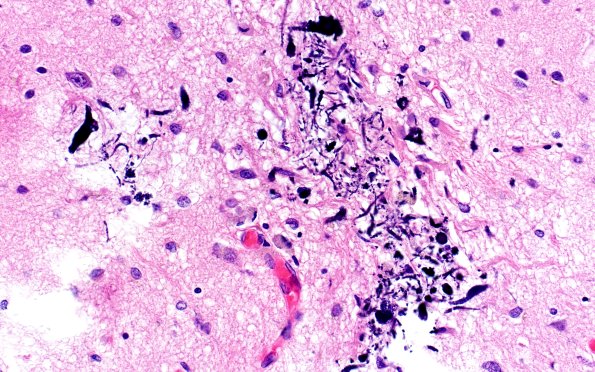

Washington University Experience | MYELIN (NON-IMMUNE MEDIATED) | Retinal Vasculopathy with Cerebral Leukoencephalopathy (RVCL, TREX1 Mutation) | 18E4 TREX1 Disease (Case 18) H&E N1 40X 2

Mineralized axons and neurons in the cortex of image #1E2. (H&E)